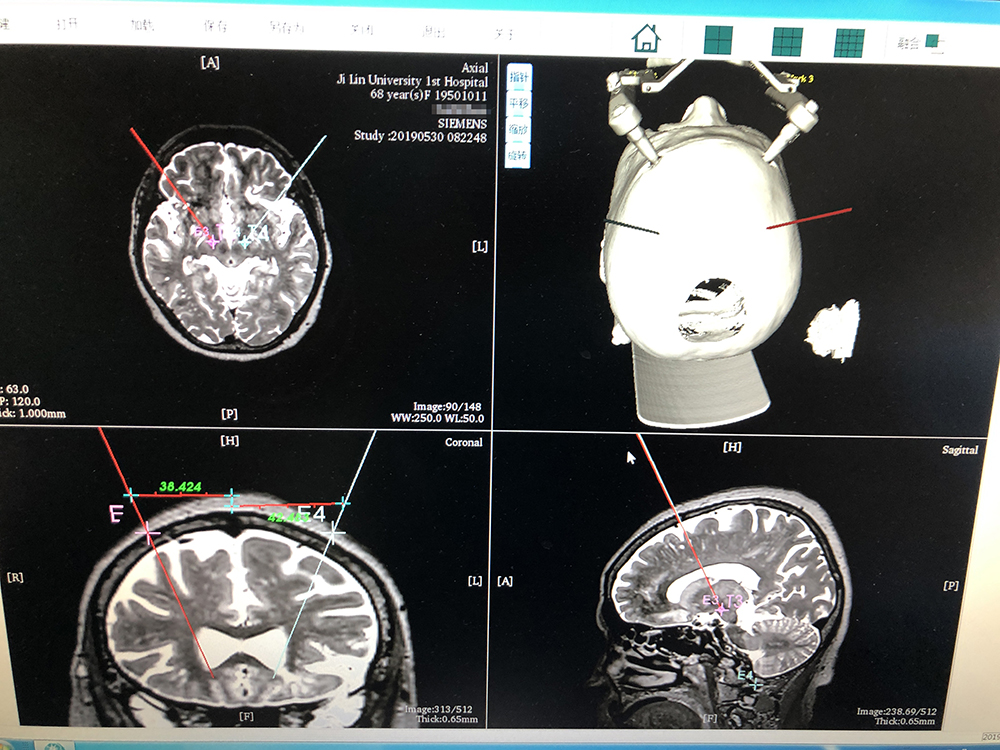

術(shù)前,邱吉慶教授借助“睿米”神經(jīng)外科手術(shù)機(jī)器人配套軟件,為患者制定雙側(cè) STN 核團(tuán)植入電極的手術(shù)路徑規(guī)劃。

alt text

借助“睿米”軟件制定手術(shù)規(guī)劃

手術(shù)規(guī)劃完成后,分別完成機(jī)械臂注冊(cè)和患者注冊(cè),系統(tǒng)顯示注冊(cè)精度分別達(dá)到0.07和0.16,符合 DBS 手術(shù)臨床的高精度要求。為進(jìn)一步確認(rèn),利用隨機(jī)驗(yàn)證點(diǎn)進(jìn)行精度驗(yàn)證,確認(rèn)誤差在1mm以內(nèi)。